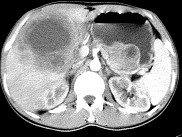

- 单项选择题女,61岁, 上腹部疼痛1个月,食欲减退, 消瘦,CT所见如图, 最可能的诊断为( )

A、原发性肝癌

B、肝包虫病

C、肝转移瘤

D、胃癌肝转移

E、肝脓肿